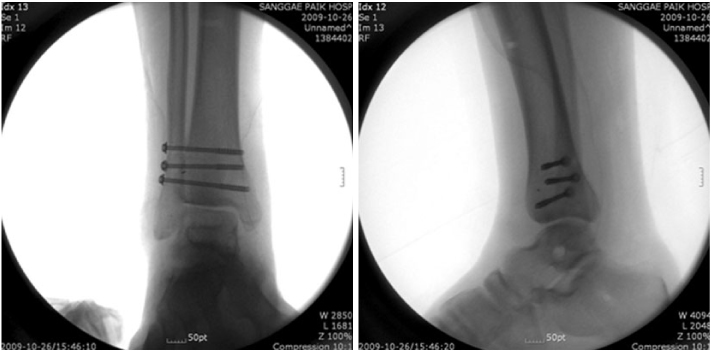

Fig. 7

Intra-operative ankle X-ray (AP and lateral views).

Fig. 7 Intra-operative ankle X-ray (AP and lateral views).